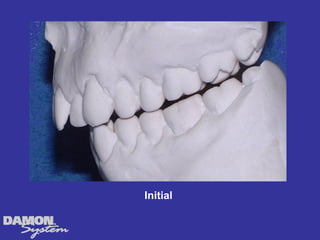

M.J. 14 yrs 6mos Class I severe crowding, deep bite, all Initial cuspids blocked out.

Initial 16 yearsโ€“ 5 months Class II, severe crowding, bilateral posterior crossbite